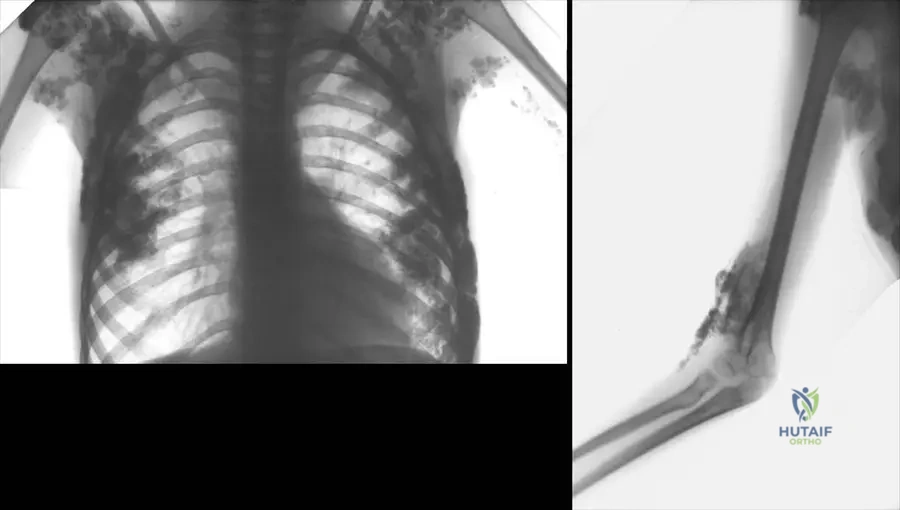

A 70-year-old male presents with chronic pain and swelling in his left knee, 5 years after a total knee arthroplasty. Clinical examination reveals a red, swollen joint with several surgical scars. Radiographs are obtained, showing septic loosening of the total knee replacement. Which of the following radiographic findings is most indicative of septic loosening in a total knee arthroplasty?

Correct Answer: C

Rationale: The clinical context and Fig. 2.56 describe septic loosening of a total knee replacement, specifically noting that "In the anteroposterior aspect (b) the femoral component is tilted and paraarticular ossification is seen as a sign of septic complication. The lateral view (c) represents huge osteolytic changes around the implants." These findings, particularly component tilting and extensive osteolysis, are characteristic of septic loosening. Absence of radiolucency (A) and stable implant position (B) would suggest a well-fixed, uninfected implant. Isolated polyethylene wear (D) is a sign of aseptic loosening or wear, not typically septic loosening. Minimal periosteal reaction (E) is non-specific and not a primary indicator of septic loosening.

A 72-year-old female presents with chronic pain and swelling in her right knee, 4 years after a total knee arthroplasty. Radiographs reveal septic loosening of the implant, including a tilted femoral component and extensive osteolytic changes. Additionally, paraarticular ossification is noted. What is the significance of paraarticular ossification in the context of a total knee arthroplasty?

Rationale: The clinical context and Fig. 2.56 explicitly state that "paraarticular ossification is seen as a sign of septic complication" in the context of septic loosening of a total knee replacement. While some degree of heterotopic ossification can occur post-operatively, significant or progressive paraarticular ossification in the setting of pain and other signs of infection is a strong indicator of a septic process. It is not a normal finding (A) in this context, nor does it specifically indicate aseptic loosening (B) or primary metabolic bone disease (D). It is clinically relevant (E) as a marker of infection.